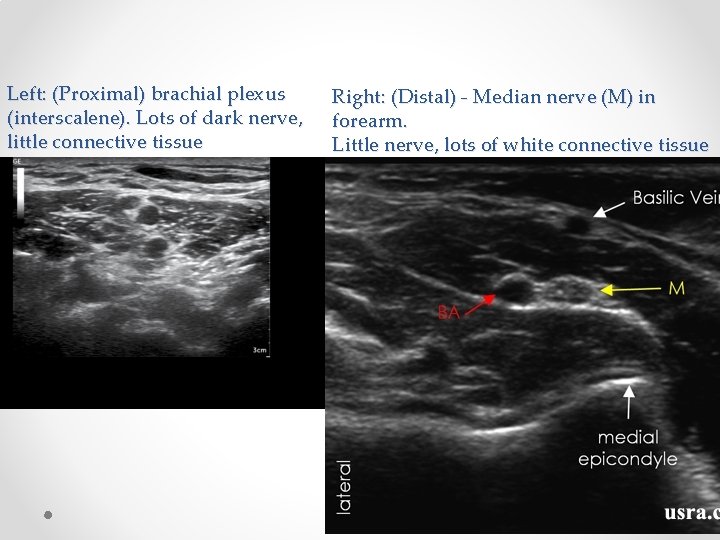

Ultrasound skills: • US blocks are composed of 2 skills o Identifying the nerves o Manipulating the needle • Identifying nerves: o KNOW YOUR ANATOMY o Practice scanning yourself o Nerves frequently run with arteries – look for an artery and nerve if often nearby- eg ilioinguinal, adductor canal, SSNB, popliteal tibial. o Nerves also tend to run in fascial planes – if you get your LA into the right plane it will usually work o Proximal nerves are mostly “nerve” (=fat=black) with little white connective tissue. As you move distally and branches are given off, nerves become a more speckled white colour due to higher proportion of connective tissue. Proximal nerves are more vulnerable to injury than distal nerves and blocks are associated with a higher risk of nerve injury o If unsure what you see is a nerve, scan proximally and distally- nerves will stay present, tendons and other things will tend to get bigger/ smaller/ disappear o If still unsure, stimulate the nerve eg 50 hz with RF needle (note RF needles can be very hard to see with US, especially for deep blocks

Left: (Proximal) brachial plexus (interscalene). Lots of dark nerve, little connective tissue Right: (Distal) - Median nerve (M) in forearm. Little nerve, lots of white connective tissue